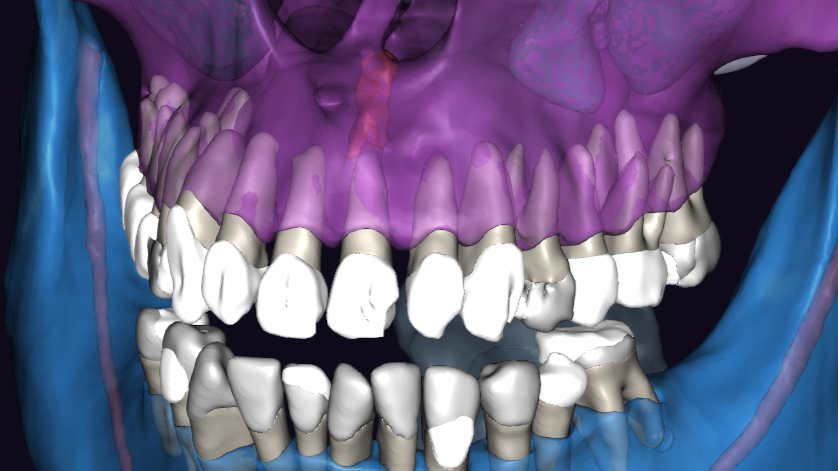

ЗД исследование перед операцией. Виден обьемный дефект в области зубов 21, 22 с вовлечением резцового канала. Размеры

Размеры кисты около1,3 мм в диаметре